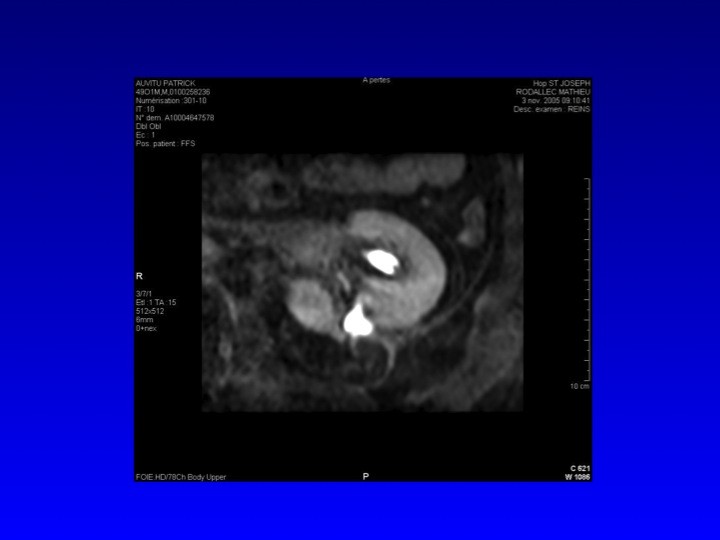

Prise en charge des petites tumeurs rénales en 2011 : diaporama 4